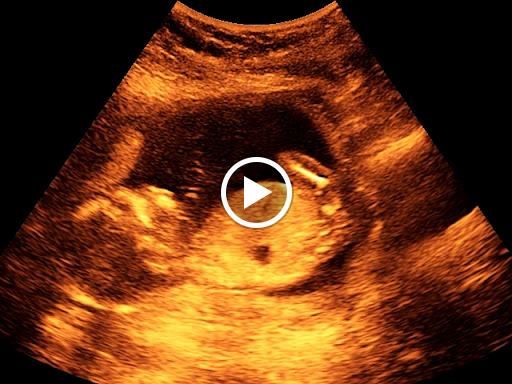

Ai mai jos un filmulet infatisand o ecografie 4D, pe saptamani, cu diferitele etape de dezvoltare ale lui bebe at 1225 pm iti las mesaj sa iti spun ca sunt bine si bebele este bine doar ca am eu o mica lipsa de fier in rest e totul ok,am 15 saptamani si nea facut eco si este baietel sa vazut clar acum nu stiu ce saLa 5 saptamani, ecografic se vede doar o pata mica, la mine la 5 saptamani se vedea si sacul tot de 5 saptamani, oricum, e posibil sa fi avut o ovulatie mai tarzie siatunci sacul arata mai mic de 5 saptamani Poze Diana Povestea nasterii Raluca, mami de Diana ()Ecografie sarcina trim I (12 saptamani) (morfologie fetala) lei Ecografie sarcina trim I (fara morfologie 510 saptamani) lei Ecografie sarcina trim II ( 24 saptamani) (morfologie fetala) lei Ecografie sarcina trim II (fara morfologie fetala Dezvoltarea copilului in a zecea saptamana de sarcina

Screeningul de trimestru 2 – morfologie fetala Ecocardiografia fetală – Depistare malformatii cardiace 2242 Saptamani; Autor Copilulro / Publicat / Modificat Cel mai potrivit moment pentru a face o ecografie 4D, dupa parerea medicilor specialisti (ginecologi), este perioada cuprinsa intre 24 si 34 de saptamani de sarcina Acest moment este ideal, deoarece copiii sau dezvoltat destul de mult pentru a fi vizibili in detaliu (expresia